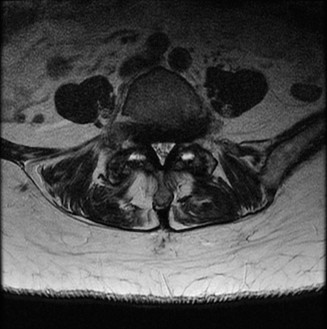

To evaluate the neural elements and the soft tissue structures, a comprehensive MRI of the lumbar spine without contrast was obtained. The T2-weighted sagittal and axial sequences confirmed the Grade 2 anterolisthesis and demonstrated severe bilateral foraminal stenosis at L5-S1. The exiting L5 nerve roots were severely compressed between the hypertrophied, fibrocartilaginous pseudarthrosis tissue of the pars defect dorsally, and the bulging, degenerated L5-S1 disc and superior endplate of S1 ventrally. Furthermore, the MRI revealed Modic Type II changes (fatty replacement of the subchondral bone marrow) in the adjacent vertebral endplates, confirming chronic biomechanical stress and discogenic degeneration. The central canal remained relatively patent, which is characteristic of isthmic spondylolisthesis, as the posterior neural arch is left behind during the anterior translation of the vertebral body.

Clinical & Radiographic Imaging Archive